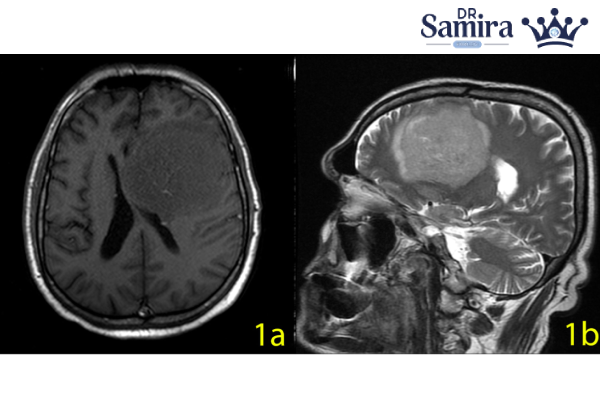

تصویربرداری

MRI بهترین روش تصویربرداری برای شناسایی مننژیوم است. ویژگیهای کلیدی در MRI عبارتند از:

- توده با اتصال دورال مشخص (Durual tail sign).

- اغلب هموژن ولی گاهی با مناطق نکروز یا سیگنال ناهمگن در گرید ۲.

- پس از تزریق کنتراست، اغلب به صورت شدید و یکنواخت تقویت میشود.